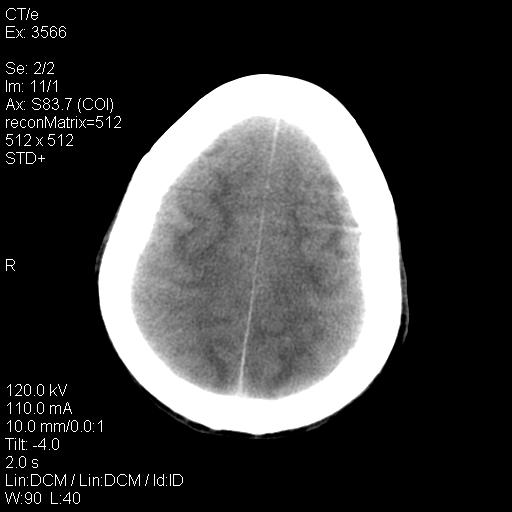

标题: CT9947:女,20岁,妊娠9个月,突然癫痫症状 [打印本页]

标题: CT9947:女,20岁,妊娠9个月,突然癫痫症状

双侧脑白质缺血缺氧性改变,并高度可疑“蛛网膜下腔出血”。

后可复性脑病,

考虑 妊娠子痫或妊高征

双侧脑白质缺血缺氧性改变.

考虑先兆子痫\\子痫致he,建议mri除外有无合并静脉窦血栓形成.

考虑pres

的确应该考虑可逆性后部脑病综合症--pres。感谢天南地北老师的指引,又学了一招儿,开心,呵呵!

考虑可逆性后部脑病综合症

支持pres